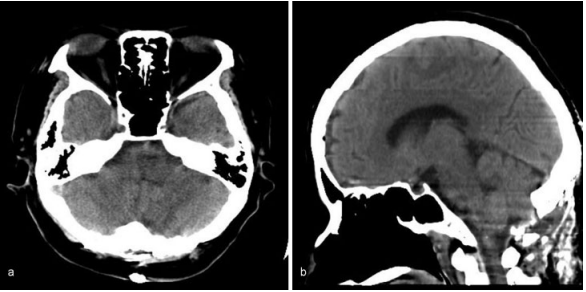

其中,一位70歲的老人因?yàn)橥蝗怀霈F(xiàn)惡心和嘔吐而被轉(zhuǎn)診到巴教授所在醫(yī)院。右舌下神經(jīng)麻導(dǎo)致右舌偏斜。她的血壓是201/100毫米汞柱。電腦斷層掃描(CT)顯示右側(cè)延髓出血。

圖:右側(cè)延髓出血的電腦斷層影像,(a)軸向(b)矢狀面。